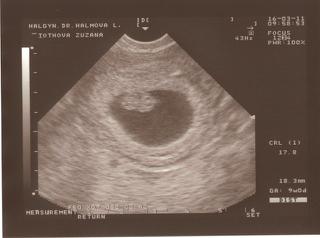

Tu sú sľúbené fotky 🙂

@santerra bábo sa hýbalo, lekárka ma na to upozornila viac krát, ale bolo to pekne vidieť, srdiečko tiež krásne bilo a fotky sa snažím nahodiť, len sa mi sem akosi nechcú nahrať nechápem prečo.....ešte skúsim zmeniť veľkosť.

Inak to že sa bábo nehýbalo a má v poriadku veľkosť aj srdiečko bilo tak je určite v pohode len čičíkalo 🙂